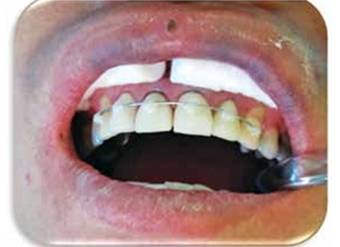

Al paciente se le deja la pieza ferulizada con el mismo alambre de ortodoncia y con los brackets por unos tres a cinco meses con la finalidad de evitar una nueva recidiva. Posteriormente se remueve la ortodoncia y se procede a efectuar la rehabilitación del central superior derecho. Se cementa un poste de fibra de vidrio en el conducto radicular y se confecciona un muñón (con el material Duo Core) el cual finalmente es preparado para recibir una corona de metal porcelana y se le toma una radiografía periapical final. (Figuras 15A y 15B)

Figura 15A: Restauración con una corona de metal porcelana.